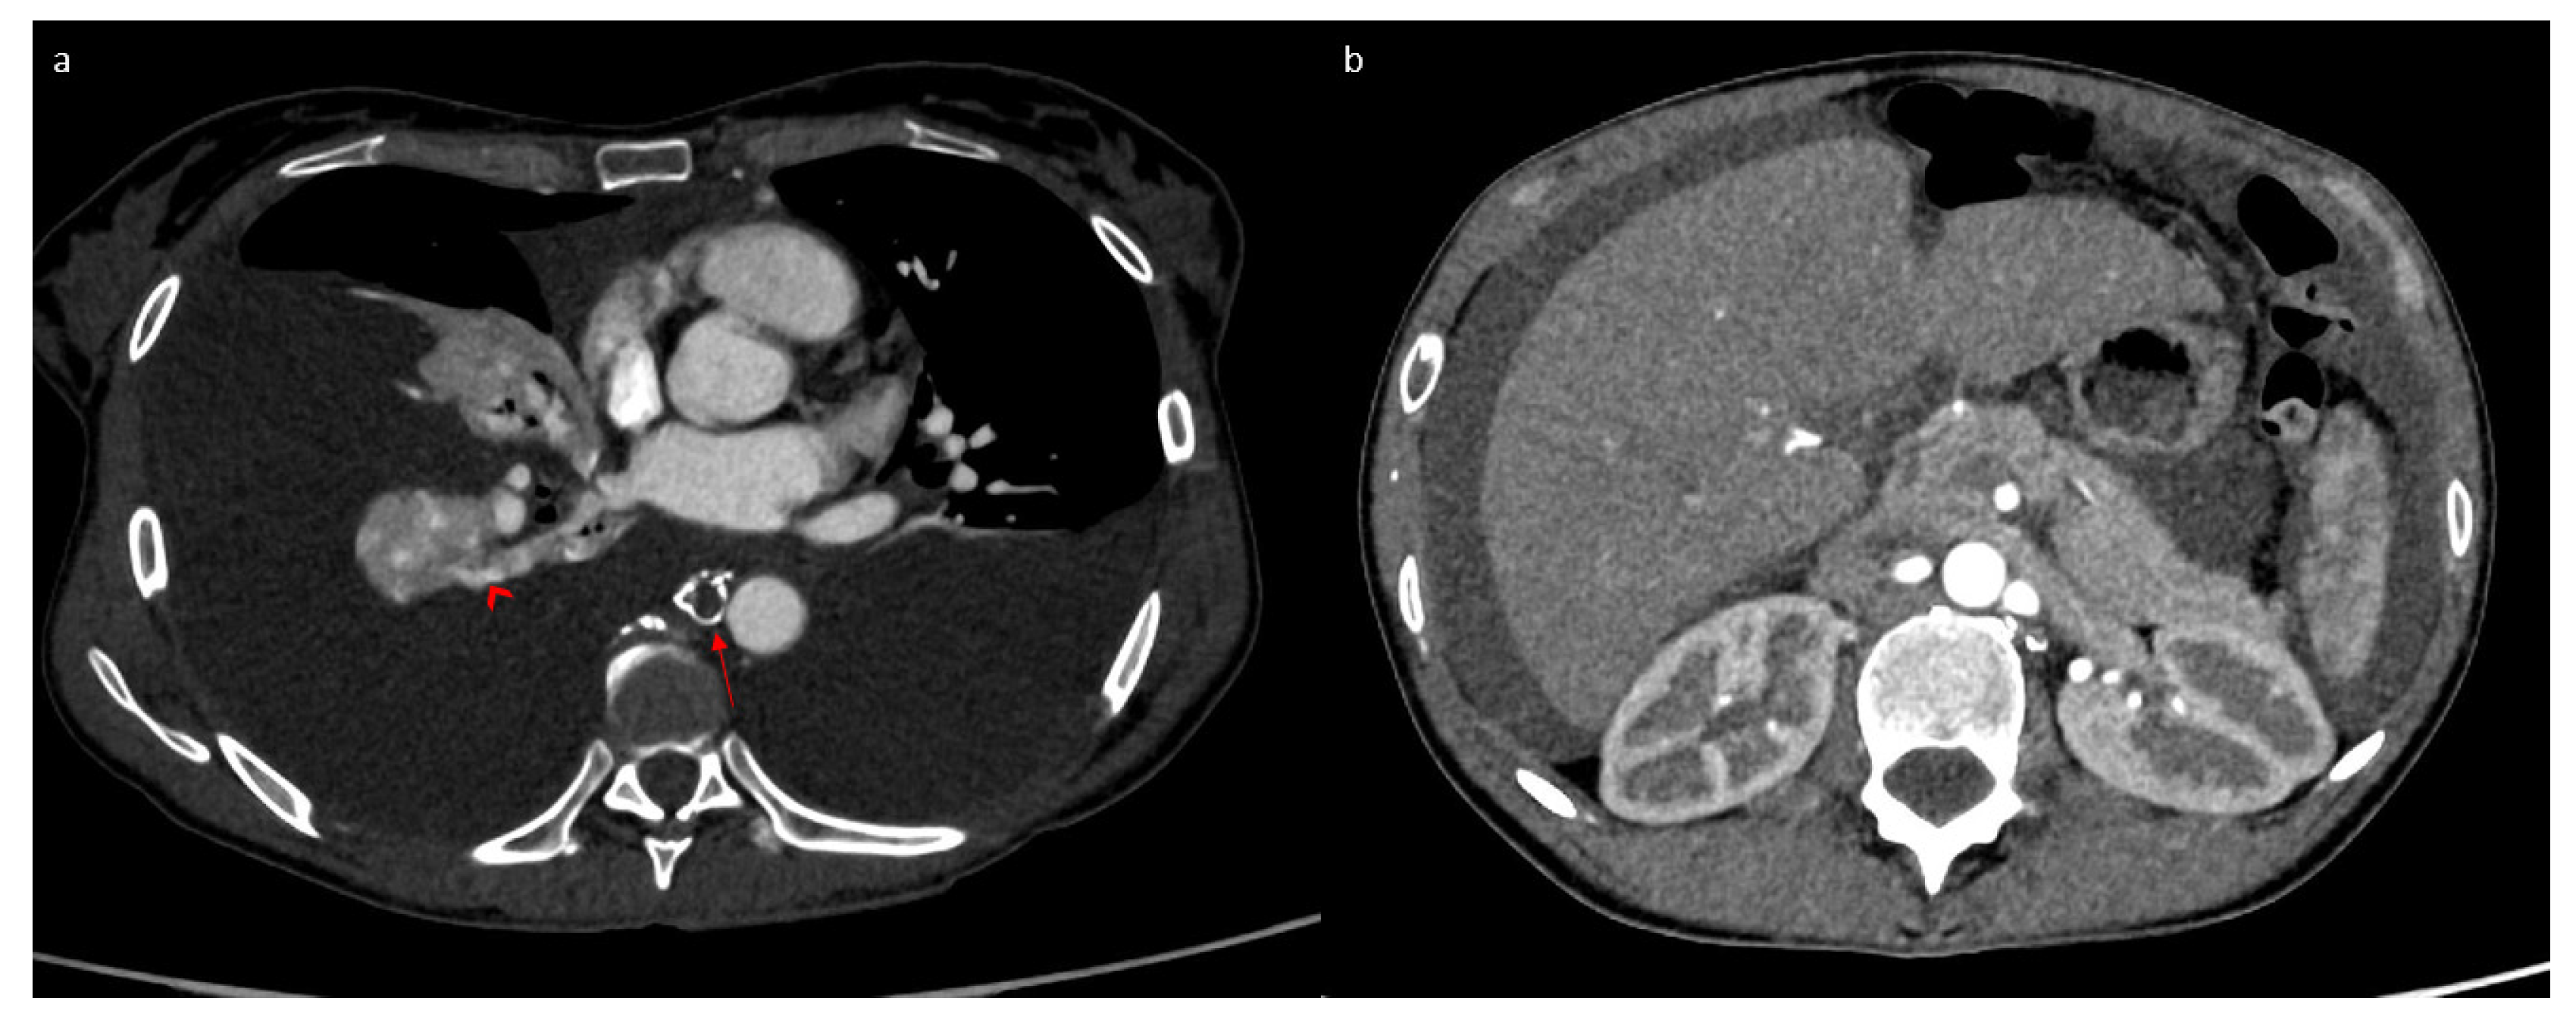

2. Case Report

3.1. Case Discussion and Physiopathological Hypothesis